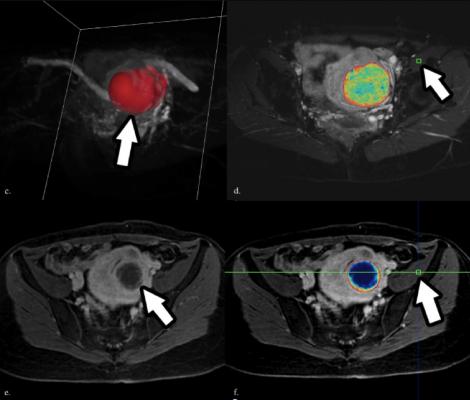

This image is used with permission from the paper "Three-Dimensional Quantitative Assessment of Uterine Fibroid Response after Uterine Artery Embolization Using Contrast-Enhanced MR Imaging." The paper can be viewed here: https://www.ncbi.nlm.nih.gov/pubmed/2563875